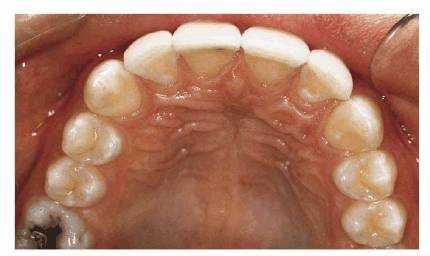

much the left central incisor protruded before restoration. Four porcelain

laminates were used to create a symmetric arch with proper spacing (see Figure 23-14F). The improvement by the final result can be

Figure 23-14F: Only four porcelain laminate veneers were necessary to eliminate the dark spaces between his teeth. Also note that the protrusion was eliminated.